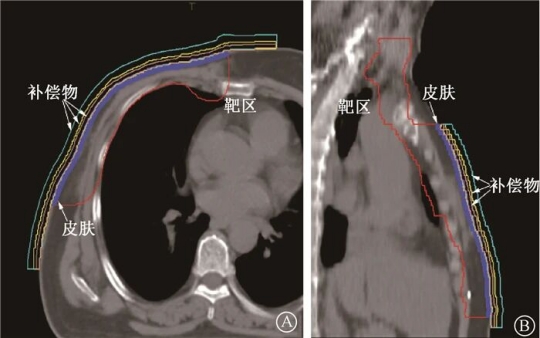

为了提高胸壁皮肤的剂量,就会贴上一层与人体组织器官接近的“膜”或“胶”,这样就在原本皮肤表面人为的制造了一个新的皮肤,原本皮肤的位置就变成皮下一定深度的区域了。射线首先到达新皮肤的表面,通过剂量建成效应,我们真实皮肤表面的剂量就提上来了。

▲ 补偿物、靶区和皮肤结构分布图 A. 横断位;B. 矢状位[4]

这块“膜”或“胶”我们叫做“组织补偿物”,常用的材料有硅胶、聚苯乙烯、石蜡或3D打印组织补偿物等。